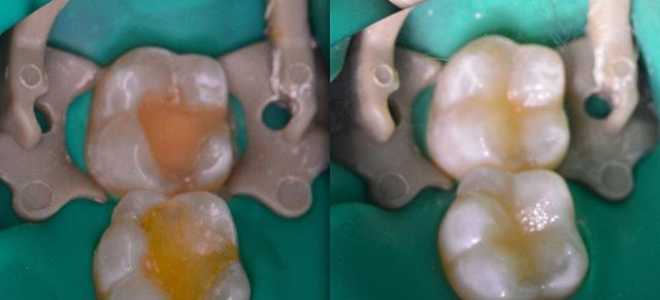

Световая пломба для зубов

Световая пломба для зубов Как выглядит световая пломба Каждый человек сталкивается с необходимостью посещать стоматолога и многие вынуждены прибегать к...